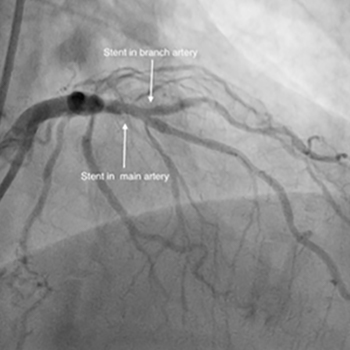

Bifurcation stenting

Learn more